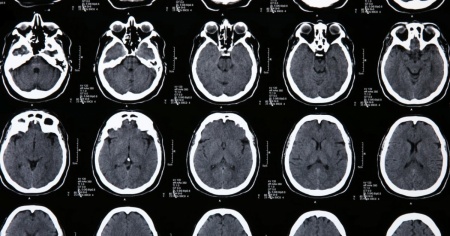

Vomito, insonnia, depressione, ansia atipica, atrofia cerebrale. Questi sono solo alcuni dei vari sintomi che negli ultimi sette anni sono stati riscontrati e accertati in 48 persone tutte residenti nel New Brunswick, Canada. Tutte, tranne due, avevano ricevuto da parte del neurologo di Moncton Alier Marrero una diagnosi secondo cui l'insieme di sintomi presentati costituivano una malattia neurologica sconosciuta, forse scatenata da fattori ambientali. Non molto tempo fa, era stata portata avanti l'ipotesi che la causa del tutto fosse legata a una neurotossina nelle aragoste. A partire dal 2019, nove persone sono decedute.

Sullo stesso sito adibito dalla provincia per informare la popolazione sull'evoluzione della malattia, era stato scritto che «i segni e sintomi clinici sono simili a quelli associati alla malattia di Creutzfeldt-Jakob, ma hanno caratteristiche atipiche. A oggi, tutti i risultati dei test sono stati negativi per forme note di malattia da prioni umana». Oggi, però, è arrivato il rapporto dei funzionari sanitari del New Brunswick, molto atteso dalla comunità, che smonta la tesi di una malattia sconosciuta.